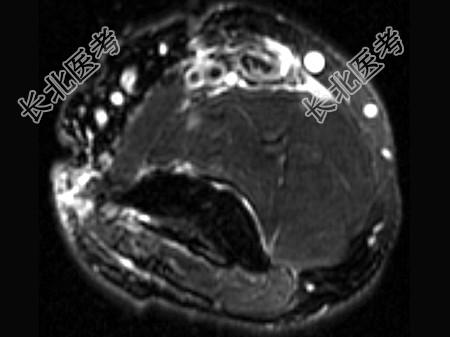

- 单项选择题女,44岁, 有外伤史,上臂远端疼痛, 结合图像,最可能的诊断是 ( )

D、肱二头肌腱远侧局部裂伤